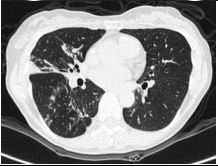

10. CC: 咳嗽 1 周,有痰